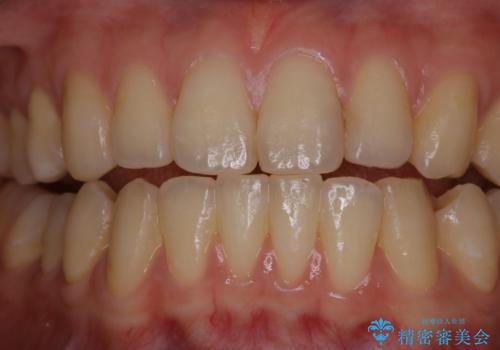

数年ぶりに歯のクリーニング(PMTC)